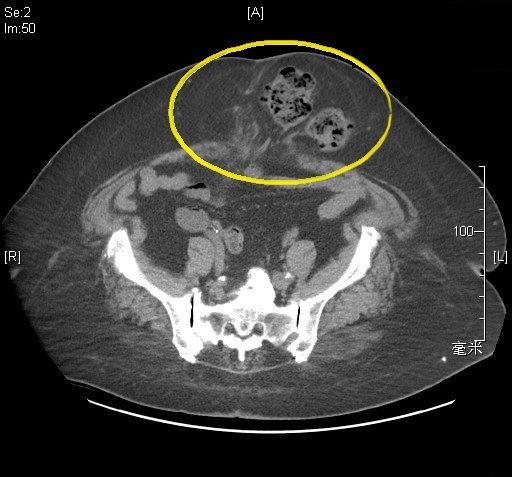

黃崧峰舉例76歲程先生個案說明,程先生多年前因腹腔腫瘤接受傳統開腹手術,術後追蹤情況一直穩定,未料近期發現過去的手術疤痕上方逐漸出現隆起腫塊,尤其在咳嗽或搬重物時更加明顯,但平躺後又會消失,反覆出現的情況讓他擔心是否為腫瘤復發,因而緊急就醫檢查。經醫師評估後發現,腫塊並非腫瘤,而是典型的「腹壁切口疝氣」。

黃崧峰指出,腹壁切口疝氣是腹部手術後常見的併發症之一,尤其曾接受傳統開腹手術的患者更容易發生。主要原因在於腹壁筋膜或肌肉在手術後未完全癒合,導致腹腔內的腸道或脂肪從腹壁缺口向外突出,形成可觸摸的腫塊。患者常見症狀包括腹部疤痕處隆起、咳嗽或用力時腫塊變得明顯,平躺後又可能暫時消失,因此容易被誤以為只是疤痕外觀變化。